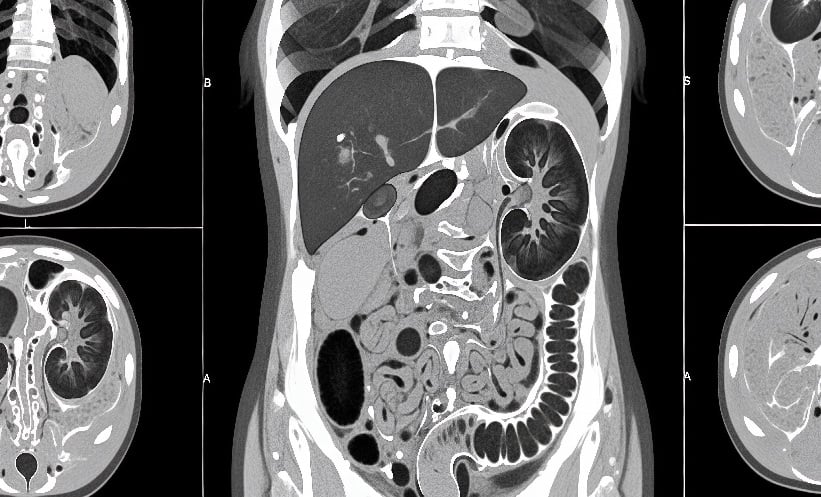

AT A SINGLE quaternary-care academic hospital, the proportion of computerised tomography (CT) scans performed on patients aged 60–90 increased from 50.4% in 2014 to 58.3% in 2024. This trend raises attention to cumulative radiation exposure in older adults, who are increasingly undergoing multiple imaging procedures. CT scans use X-rays to generate detailed internal images and are critical for diagnosing conditions such as fractures, cancers, and cardiovascular disease, but repeated scans can incrementally raise radiation risk.

Featured image: Mbahjuri on Adobe Stock